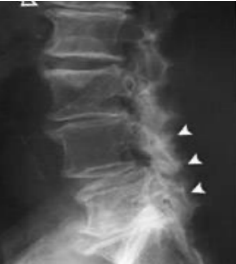

Lesão degenerativa discal

aonde estão as lesões nas imagens?

A

1. Lesão degenerativa discal de C5-C6- C7

2. Lesão degenerativa discal de L2-L3-L4-L5